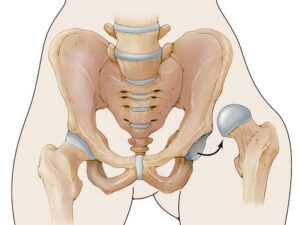

دررفتگی مادرزادی لگن؛ علائمی که والدین نادیده میگیرند

دررفتگی مادرزادی لگن یکی از ناهنجاریهای اسکلتی است که از بدو تولد وجود دارد و در صورت نادیده گرفتن میتواند روند رشد طبیعی کودک را دچار مشکل کند. در این